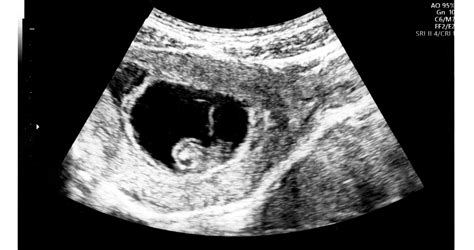

A könyv kiemelkedő szerepet játszik a várakozással teli kilenc hónap eseményeinek naplóban való rögzítésében. Az összegyűjtött emlékeket így könnyen feleleveníthetjük, felidézhetjük a szép érzéseket, vagy a leírt tapasztalatainkat összehasonlíthatjuk korábbi és későbbi várandóságainkkal. Minden hónapban lehetőséget ad feljegyzések készítésére az aktuális vizsgálatokról, a kismama súlyáról, érzéseiről és félelmeiről. Beleírhatók az aktuális ultrahang (UH) vizsgálatok mérési adatai, ami különösen hasznos lehet, ha a jövőben újabb babát tervez a család, hiszen így összehasonlíthatóvá válnak a mérési eredmények. A könyvbe bele lehet ragasztani a kismama és a baba UH képeit hónapról hónapra, a végén pedig az első hetek eseményeit is rögzíteni lehet.

A "Pocakosnapló" nem csupán egy emlékgyűjtő füzet, hanem hasznos információkat is tartalmaz a leendő szülők számára. Segít abban, hogy melyik hónapban milyen vizsgálatot kell elvégezni vagy elvégeztetni. A kiadvány részletesen bemutatja a kismamára váró változásokat, vizsgálatokat, és azt, hogyan fejlődik a pocaklakó a 40 hét alatt. A 3D-s ultrahang fotókkal illusztrált részek bemutatják a baba viselkedését, szokásait is. Többek között megtudhatjuk, hogy álmodnak-e, éreznek-e ízeket, illatokat, vagy hogy mit látnak a kismama pocakjában.